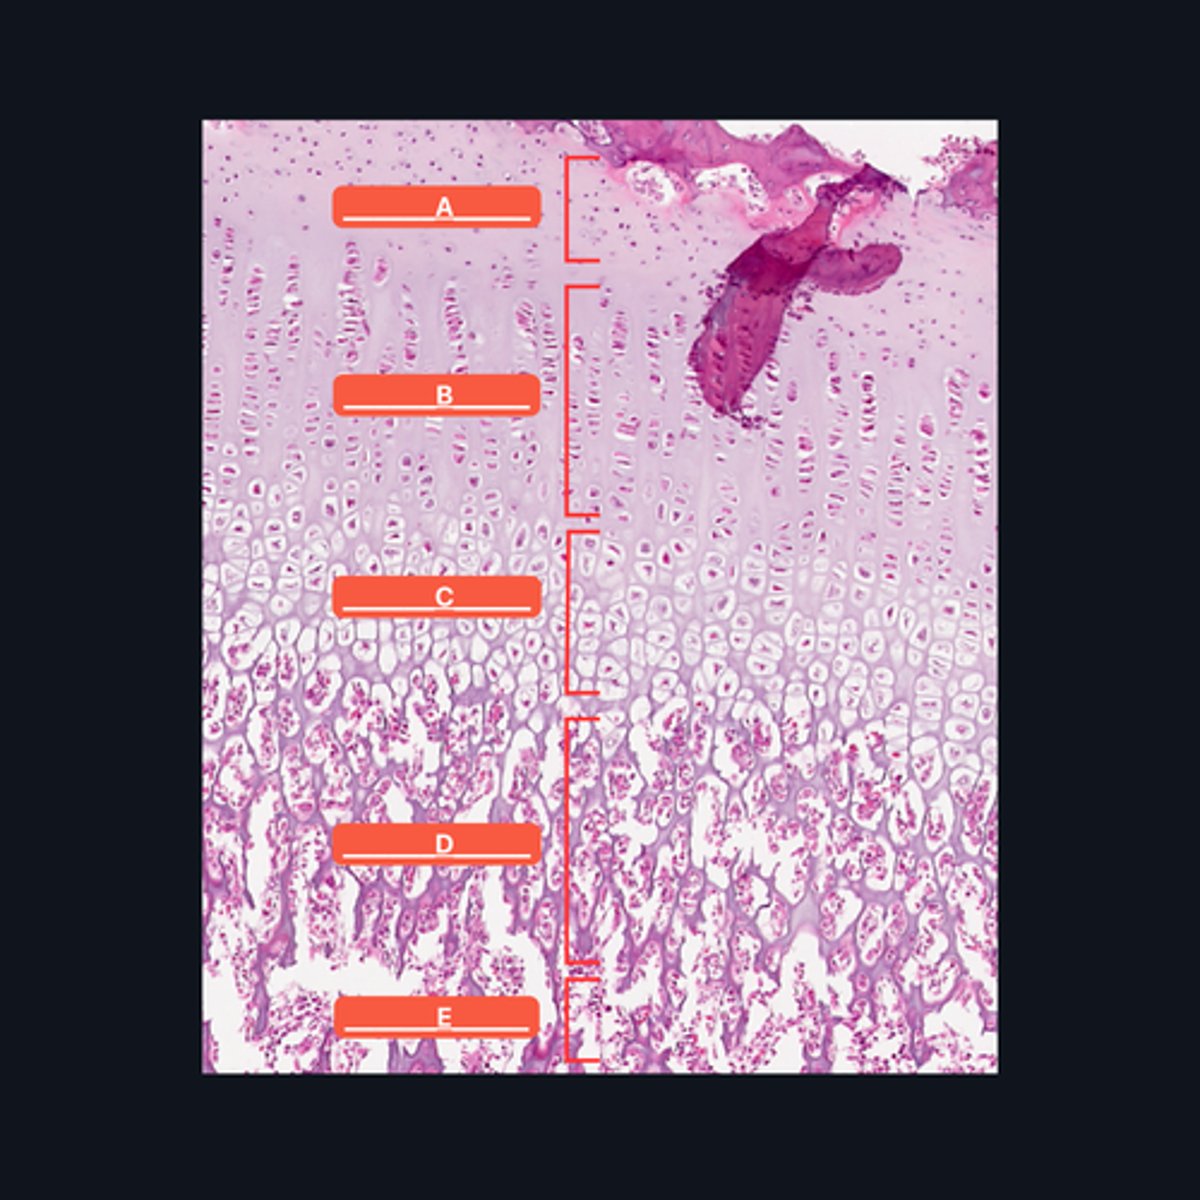

A - Zone of Resting Cartilage Cells

B - Zone of Proliferation

C - Zone of Maturation

D - Zone of Calcification

E - Zone of Ossification

Identify the pointed structures

B - Zone of Proliferation

Which pointed structure is the zone where instestitial growth occurs and what zone is it?

E - Zone of Ossification

Which pointed structure and what zone where many of the cavities left by cartilage cells merge to form marrow cavities?

C - Zone of Maturation

Which pointed structure and what zone do not divide anymore?

A - Zone of Resting Cartilage Cells

Which pointed structure and what zone anchors the epiphyseal plate to the epiphysis?

D - Zone of Calcification

Which pointed structure and what zone where the cartilage matrix is calcified